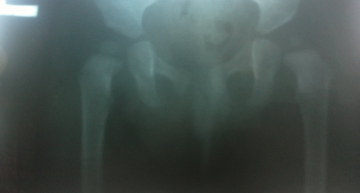

Здравствуйте! Беспокою Вас с г.Борисова. У меня сын 6,5 мес. На плановом осмотре у ортопеда в 6 мес. выявлены ассиметричность ягодичных складок ( слева смещены на 0,7 см вверх) и ограниченность отвода левой ножки до 70 градусов. Отправили нас на ренген. По ренгену: точки окостенения головок бедренных костей равновеликие, крыши вертлужных впадин не скошены (АУ 22 градуса справа и 19 градусов слева), без деформаций, линии Шенгона прерываются с обеих сторон. Заключение: предвывих т/б суставов справа и слева.Рекомендовано широкое пеленание и гимнасика. Ребенок имеет генетическую предрасположенность к данному заболеванию, т.к у меня в детстве был диагноз врожденный вывих бедер. Оперирована, сейчас в возврасте 26 лет стою на учете у ортопеда с диагнозом коксартроз 3 степени слева и 2 степени справа.